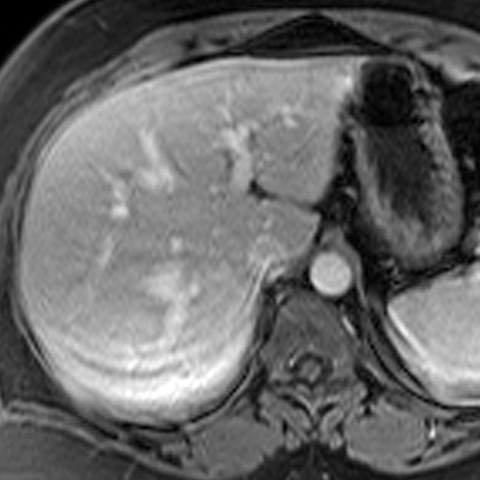

Normal Liver (T1-Weighted MR) [1 of 4]